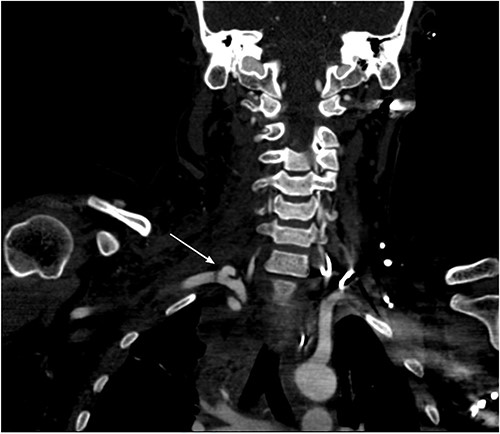

She remained hemodynamically stable; therefore, the patient was transferred to Computed tomography (CT) scan for optimal preoperative planning. Head and neck CT showed right common carotid dissection with a small pseudoaneurysm (Fig. 2). And bullet fragment causing proximal filling defect measuring 1.4 cm long without active extravasation. Surrounding the right common carotid was a hematoma extending to the anterior neck and superior mediastinum. Also, Right subclavian dissection with three pseudoaneurysms (Fig. 3) proximal and distal to the right vertebral artery takeoff, the largest measures 1.1 × 0.8 cm. Multiple scattered metallic fragments were also noted at the subcutaneous tissue of bilateral temporal bones and the occipital area.

Chest CT showed three bullet fragments. One was adjacent to the right acromioclavicular junction, another was posterolateral to the right periscapular muscles, and the third was anterior to the left scapula (Fig. 4). In addition to right lung contusions, left fifth rib fracture with pneumothorax, and bilateral pleural hemothorax more at the left side.

Bullet fragments adjacent to the right acromioclavicular junction and posterolateral.